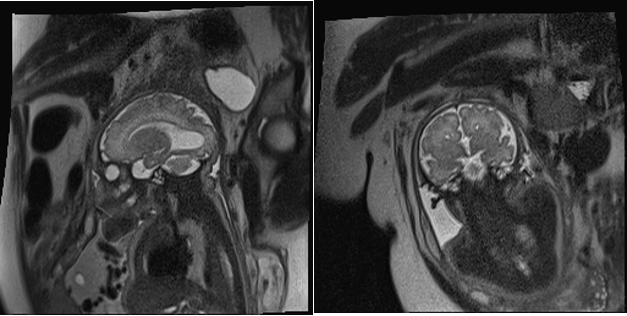

Fetal MRI was performed in three cases. It confirmed the ultrasound suspicion of ACC and revealed no additional anomalies. The remaining two corresponded to ventriculomegaly—one severe and one associated with dilation of the suprapineal recess—suggesting a possible but unconfirmed obstructive etiology (Figures 1-3).

Figure 2. Complete agenesis of the corpus callosum associated with bilateral colpocephalic ventriculomegaly.

<b>Figure 2.</b> Complete agenesis of the corpus callosum associated with bilateral colpocephalic ventriculomegaly.

In the present study, one case of ACC was identified in a female infant. The prenatal diagnosis was made by ultrasound at 31 weeks of gestation, revealing complete agenesis associated with moderate bilateral ventriculomegaly. Fetal magnetic resonance imaging confirmed the absence of the corpus callosum and the presence of moderate bilateral ventriculomegaly. Genetic testing identified a paternally derived deletion on chromosome 15.